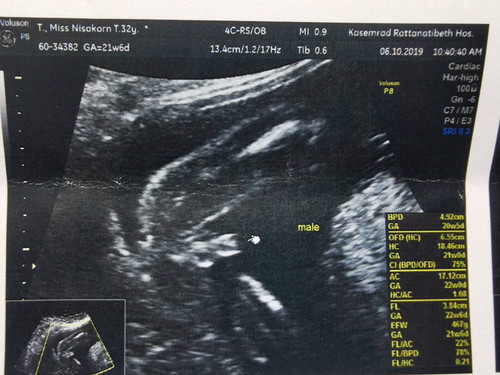

อยากได้ลูกสาวมากค่ะ แต่ซาวด์ออกมาได้ผู้ชาย คิดว่าได้ลูกสาวชัวร์ๆ รู้สึกผิดหวังอย่างรุนแรง วันนี้คุณสามีและคุณลูกชายปลอบใจแม่ทั้งวัน แต่ก็ยังไม่ดีขึ้นค่ะ คิดหลอกตัวเองเสมอว่าคลอดออกมาอาจเป็นลูกสาวก็ได้(ทั้งๆที่รู้ว่าเป็นไปไม่ได้แล้ว?). มีวิธีทำใจให้ยอมรับยังไงได้บ้างคะ ???